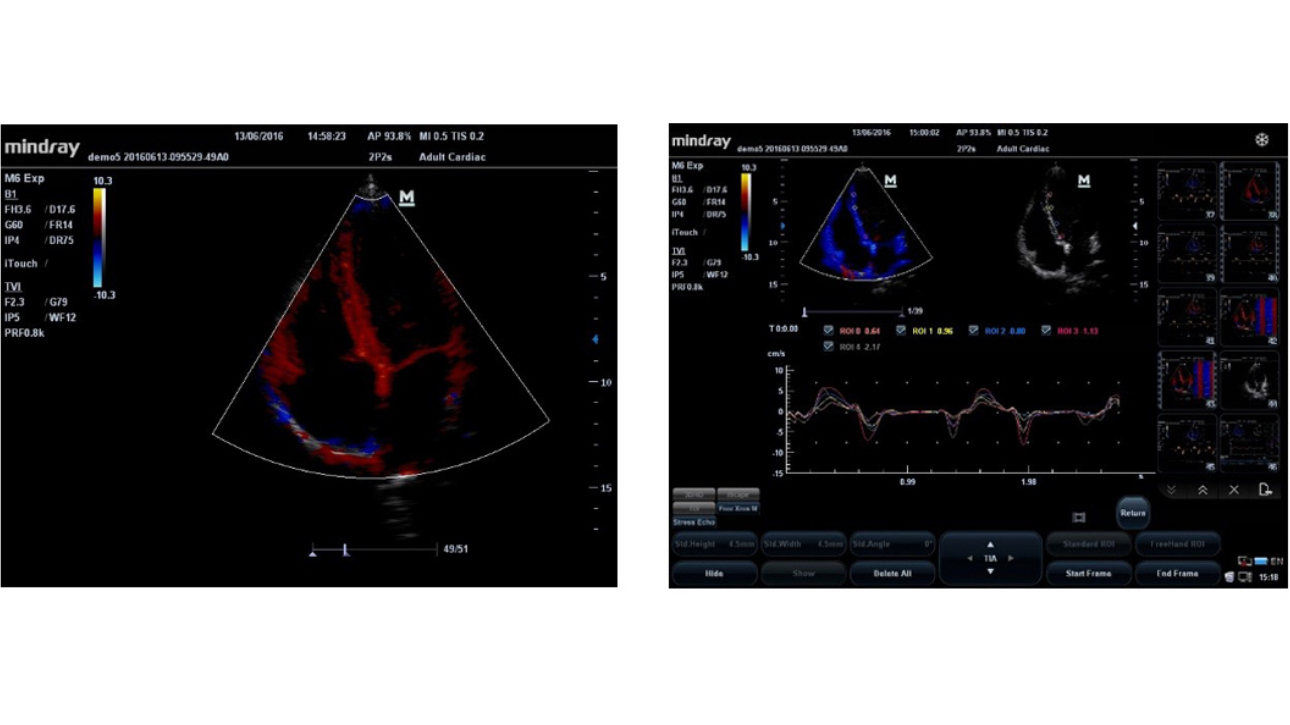

An innovative technology to better visualize tiny vessels and complex flow patterns, based on Mindray's exclusive processing algorithm.

UWN contrast imaging enables M6 to detect and utilize both 2nd harmonic and non-linear fundamental signals, generating images with significant enhancements.

- More sensitive minor signal, reduced agent dosage

- Longer agent duration with lower MI requirement